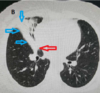

* ¿Qué estudio es? * ¿Qué patrón ves?

- TC - **Vidrio despulido** | (todavía se ven los vasos)